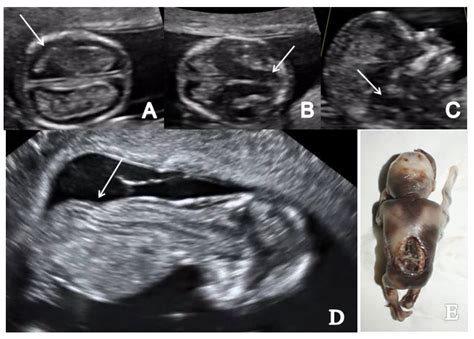

• Nuchal Translucency Screening: This scan is often combined with a nuchal translucency (NT) screening, which measures the fluid-filled space at the back of the fetus's neck. This measurement, along with maternal blood tests, can help assess the risk of chromosomal abnormalities such as Down syndrome.

• Nuchal Translucency (NT) Measurement: This screening assesses the risk of chromosomal abnormalities. A thicker NT measurement may indicate a higher risk, but further testing is usually required for confirmation.

• Abnormal Findings: If any abnormalities are detected, such as an increased NT measurement or structural issues, further testing may be recommended. This could include:

Chorionic Villus Sampling (CVS) To detect chromosomal abnormalities by analyzing a sample of the placenta.

Amniocentesis To diagnose genetic disorders by examining the amniotic fluid.

Detailed Anomaly Scan To provide a more comprehensive evaluation of the fetus's anatomy, usually performed around 20 weeks.